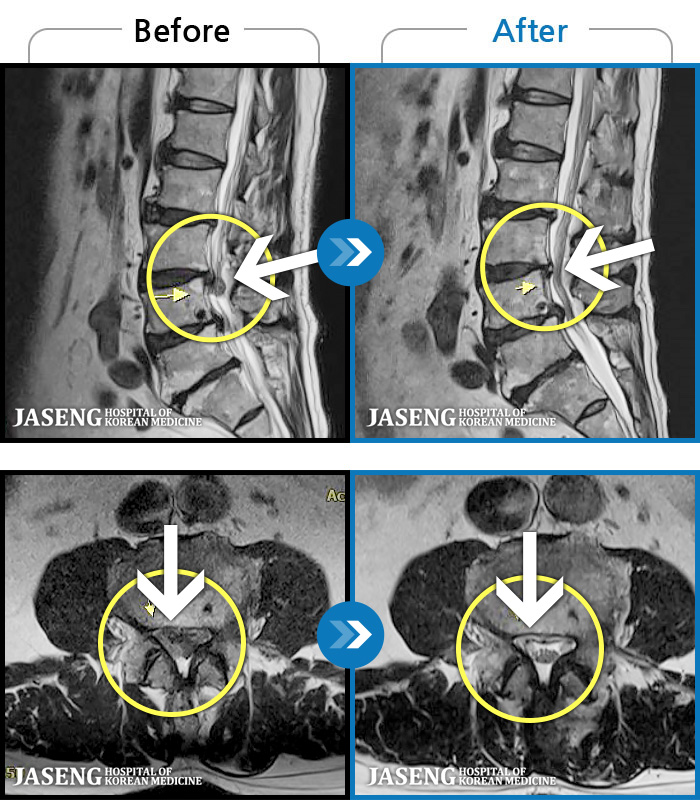

Before

After

환자에게 사전 동의를 받아 동일 조건에서 촬영되었습니다.

개인에 따라 치료 후 부작용이 발생할 수 있으니 의료진과 상담 후 치료를 진행하시기 바랍니다.

좌측 골반 및 종아리부터 발까지 이어지는 저림과 통증으로 내원하셨습니다.

엉덩이의 왼쪽 부위 및 하지방사통이 심각하여 보행이 불가한 상태에서 내원하셨습니다.